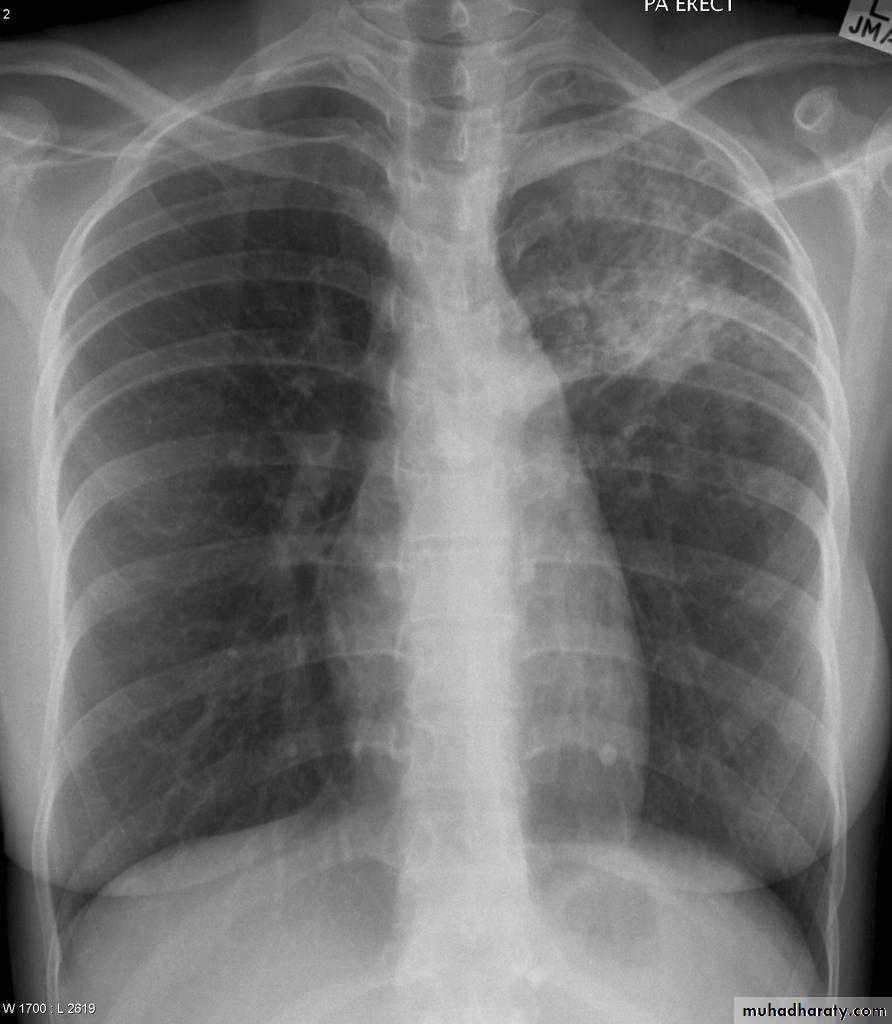

Right middle lobe consolidation

The right middle lobe is bordered superiorly by the horizontal fissure, and medially by the right heart border. Any abnormality, which increases density of this lobe, may therefore obscure the right heart border, or be limited superiorly by the horizontal fissure.

Radiographic features

Features of right middle lobe (RML) consolidation on CXR include:

opacification of the RML abutting the horizontal fissure

indistinct right heart border

loss of the medial aspect of the right hemidiaphragm

air bronchograms